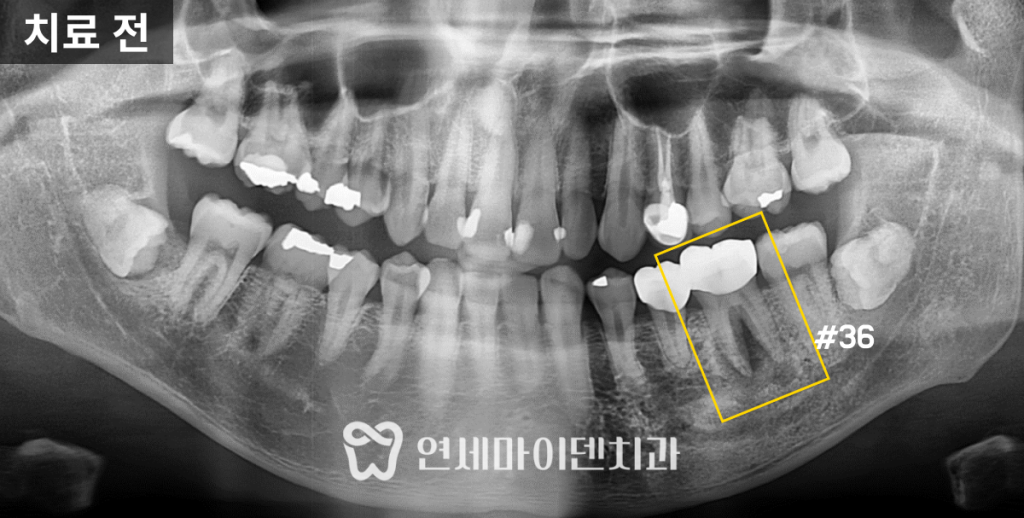

잇몸 고름으로 발치 진단

환자분은 한 달 전부터 하악 어금니 주변으로

잇몸 고름이 나오는 증상을 겪고 있었습니다.

해당 부위의 잇몸은 많이 부어 있었고,

잇몸 속 고름이 주기적으로 배출되는 상황이었습니다.

타 병원에서는 염증이 심하다는 이유로 발치를 권유하였고,

파노라마 사진에서도 하악 제1대구치 뿌리 주변의 뼈가

까맣게 녹아 있는 소견이 확인되었습니다.

보통 치아 뿌리 끝만 뼈가 녹아 있는 경우에는

신경치료를 통해 치아를 살릴 수 있는 가능성이 높지만,

이번 사례는 치근이 분기되는 중앙 부위의 뼈까지

녹아 있었기 때문에 상태가 좋지 않은 편이었습니다.